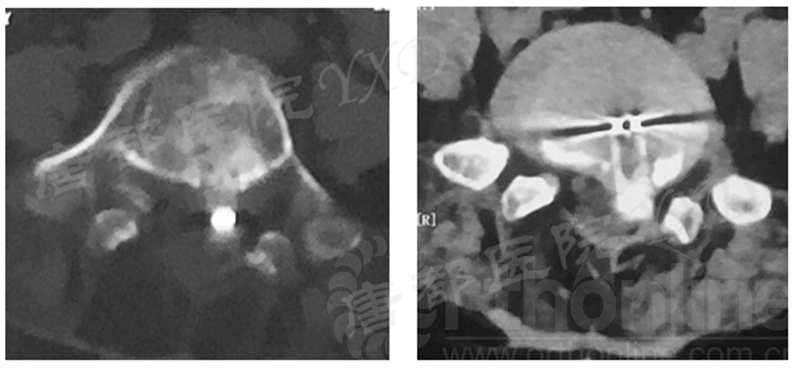

影像学检查:

诊断:腰椎椎间融合术后融合器后移

手术方案:显微镜辅助MI-TLIF腰椎翻修术

术中视频:http://api.orthonline.com.cn/attach/Case3.mp4(术中发现因前次手术全椎板及关节突切除,TLIF的第一步,即关节突关节的定位落脚点难以找到。显微镜下通过Kambin三角解剖位置,进行从外至内的解剖,寻找cage尾端;此外,因大量瘢痕渗血,难以进行充分止血;但在显微镜的照明和放大视野下,操作均可在不伤及神经的前提下进行。由于终板骨质吸收,椎间隙塌陷,导致术野内可同时看到出行根和走行根。而在显微镜下,能够通过调整景深和视线角度,精准充分处理椎间隙骨性终板。无手术并发症)